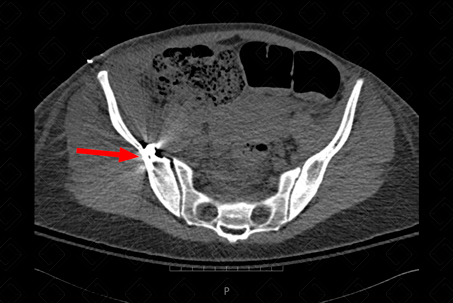

Descrição das figuras 1 e 2: Presença de artefato metálico no ramo ilíaco à direita, compatível com PAF (seta vermelha). Observamos no ramo isquiopubiano, deste lado, traço de fratura associado (seta amarela).